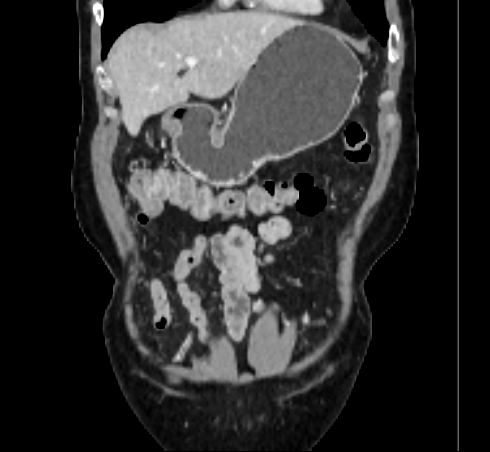

Over the years, there have been attempts to develop automatic methods for small bowel segmentation, especially using deep learning. The small bowel was included in segmenting multiple organs-at-risk for radiotherapy treatment planning of affected tissues, such as pancreatic and cervical cancers, in CT scans [8, 9, 13]. Although the results obtained for the small bowel are reasonable, some of their data included only the part of the small bowel that is closest to the target area, which needed to be dose-evaluated [8, 9]. In [13], the rough bowel location was detected instead of performing pixel-accurate small bowel segmentation. There have been only a few previous works dedicated solely to automatic small bowel segmentation [12, 14, 21]. While the specific anatomic relationship between the mesenteric vasculature and the small bowel is used to guide the small bowel segmentation in [21], a cylindrical shape constraint is applied during training of the small bowel segmenter in [14]. Although each of the works showed reasonable performance for particular datasets, their generalizability across different datasets was not evaluated. A CT scan is acquired using a specific imaging protocol depending on the purpose of the investigation, which includes the use of different contrast media and scan timing. Thus, the appearance of the small bowel may be different across datasets as exemplified in Figure 1. It is observed in our experiment that, when trained on one dataset, the model does not generalize well to another dataset due to the domain shift (section 3).

In this paper, we present a novel unsupervised domain adaptation method for small bowel segmentation, which is based on feature disentanglement. Although the absolute intensity values in CT scans (Hounsfield units) carry important information on specific substances of the human body, thus could provide a clue of being specific tissues and organs, they may be variable according to the imaging protocol. Figure 1 shows example CT scans that were acquired with and without oral contrast administration. The absolute intensity values are no longer a strong clue for the small bowel when we train and test across the datasets. Non-intensity features like texture and shape may be more useful. For example, local textures of the valvulae conniventes, which are circular folds on the inner surface of the small bowel, are more recurrent across the datasets.

Figure 3 shows example segmentation results in 3D. The result corresponding to ‘feat. & out. level DA’ in Table 1 is compared to ours. We note that the only difference between them is whether the feature disentanglement is involved for the domain adaptation, thus could show its effectiveness. Fewer errors are observed for the proposed method. We believe this is because the proposed method explicitly concentrates on the features more transferable across the datasets, the non-intensity features in this work, by disentangling those features and applying adversarial learning directly to them during the adaptation process. Example reconstruction results from the auto-encoding architecture as well as segmentation results in coronal view can be found in supplementary material.